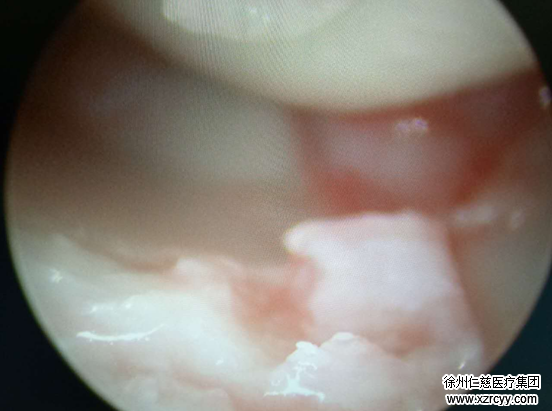

6月23日,入院后第二天,齐伟亚主任在腕关节镜下为张女士做了囊肿切除手术。术后第三天,张女士即出院。

专家提醒:手腕腱鞘囊肿是一种好发于手腕背侧、掌侧或足背等处的良性肿块。典型表现为无痛性的半球形肿块。虽然本病治疗方法很多,但多数治标不治本有复发的可能。若囊肿较大或是多次复发,建议采取手术治疗。手术能将全部囊壁连同周围部分正常的腱鞘、腱膜等组织、彻底切除。术后很少复发。